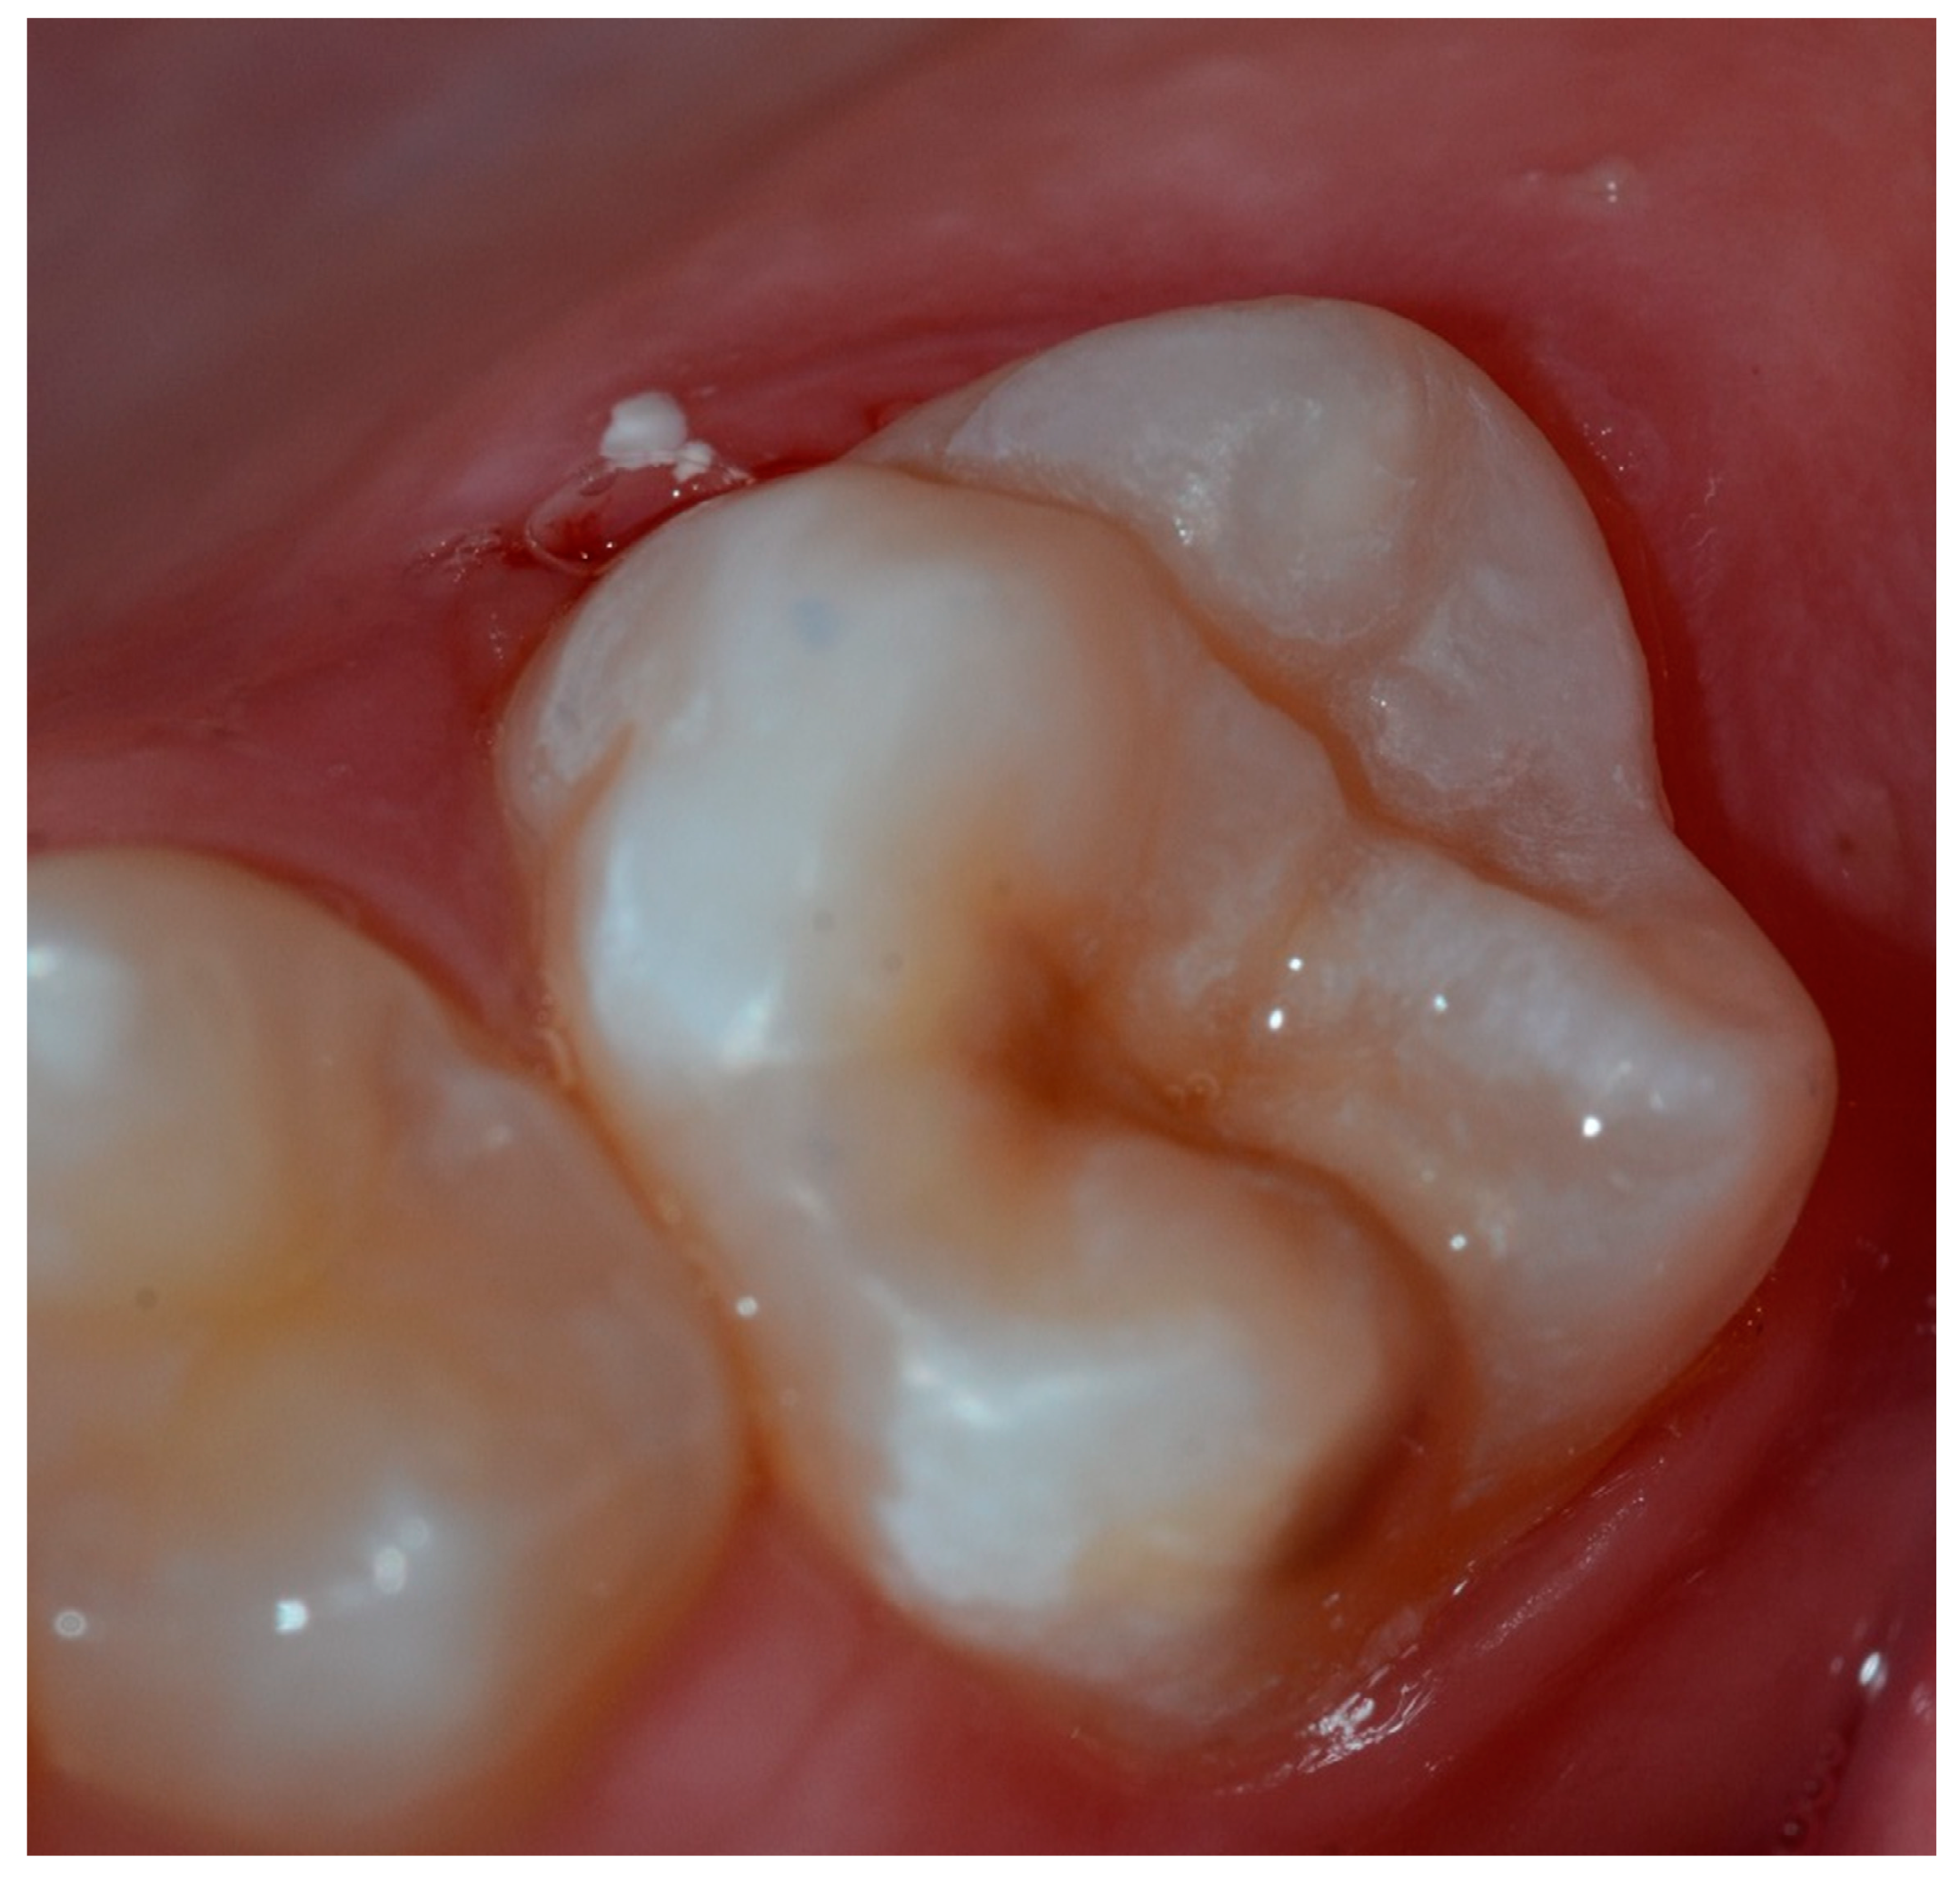

Hypersensitivity in Molar Incisor Hypomineralization: Superficial Infiltration Treatment

1. Introduction